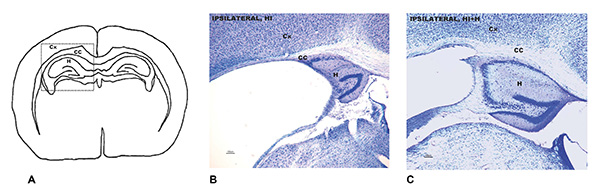

A: zona del cervell afectada per la lesió cerebral per hipòxia i isquèmia. B: Anàlisi neuropatològica que mostra el dany cerebral en ratolins adults que essent nadons van patir la lesió i no van rebre estimulació sensorial. C: Anàlisi neuropatològica de la mateixa zona en els ratolins adults que sí la van rebre.

Els resultats mostren que aquesta intervenció exerceix una notable protecció neurològica en ambdós sexes al llarg de la vida, però és especialment positiva en mascles, destaquen les investigadores. En aquest sexe l’anàlisi histopatològica va mostrar un dany cerebral un 50% menor que en els ratolins no sotmesos a l’estimulació. En femelles va ser d’un terç. La protecció neurològica en ambdós sexes es va correlacionar amb millores en les capacitats funcionals, a nivell de reflexos, i va permetre millorar els resultats de memòria.

Per àrees cerebrals, la regió involucrada en el control motor i l’aprenentatge i la memòria -el caudat-putamen-, va ser la que va registrar una major diferència en mascles, amb un 80% menys d’afectació. En femelles, la principal millora va ser la disminució, en un 66%, de l’atrofia del cos callós, que permet als dos hemisferis cerebrals treballar de forma conjunta i complementària.